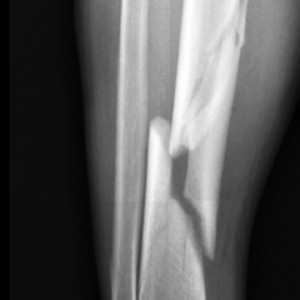

Naukowcy przeanalizowali dane z ponad 1,6 miliona Amerykanów w wieku 65 lat i starszych, którzy mieli osteoporozę i doświadczyli złamań w latach 2005 i 2009. Spośród tych pacjentów, 87 procent stanowiły kobiety.

Śmiertelność w rok po złamaniu wynosiła 18,7 procent wśród mężczyzn i 13,9 procent wśród kobiet. Kobiety były pięć razy bardziej narażone na złamania początkowo niż mężczyźni, ale miał nieco mniejsze ryzyko kolejnych złamań w ciągu trzech lat od pierwszego złamania.